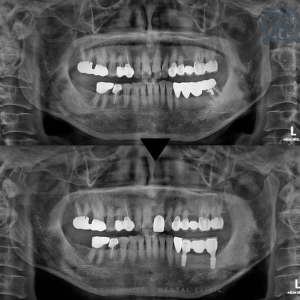

영도치과, 자연치와 조화를 이루는 임플란트 식립 사례

영도치과, 자연치와 조화를 이루는 임플란트 식립 사례 안녕하세요, 영도치과 서울화이트S치과입니다! 우리 치과에는 건강한 치아를 가지고 내원하시는 분들도 계시지만, 여러 치아에서 예후가 좋지 않은 징후가 나타나는 경우도 종종 있습니다.…